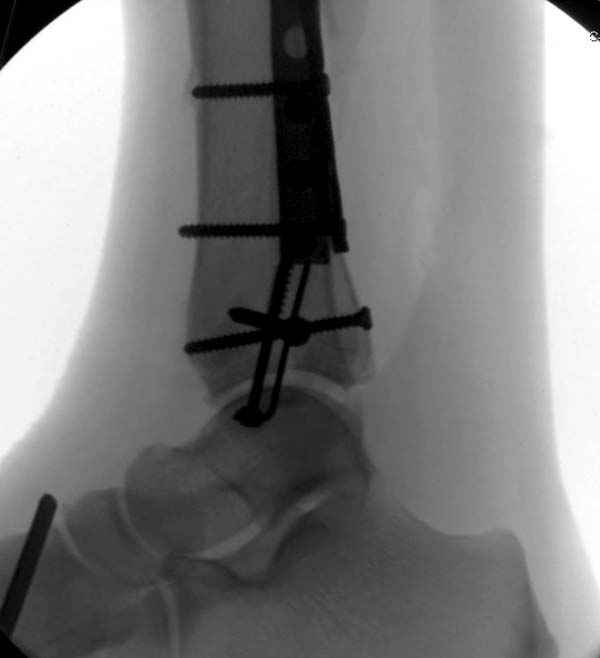

Из заднего доступа остеотомия тонким остеотомом и коррекции на ЭОПе.

Без применения сложной конструкции, а обычными параллельными шурупами. Шурупы в 3.5 мм и дополнительно фиксация крючковидной пластиной, сделанной из 3.5 mm semitubular пластиной, Butress или аntiglade фиксация.

Здесь алгоритм фиксации свежего перелома и преоперационный план для обсуждаемого случая.